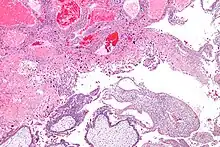

| Micrograph of intermediate trophoblast and a hydatidiform mole (bottom of image). H&E stain. | |